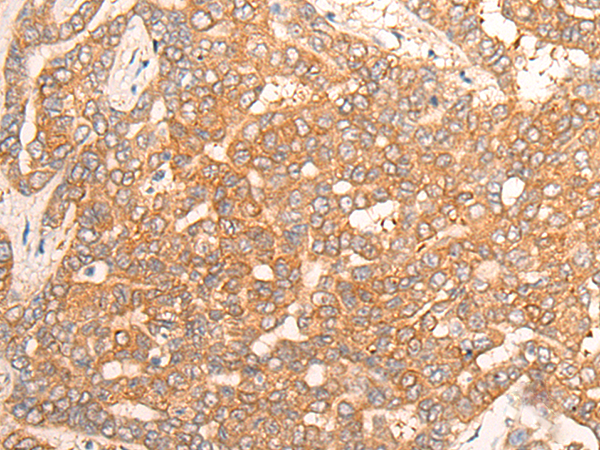

| IHC | 咨询技术 | Human,Mouse,Rat |

| Species Reactivity | Human, Mouse, Rat |

| Immunogen | Synthetic peptide of human CPS1 |